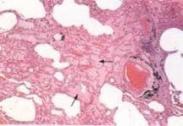

• 肺炎桿菌肺炎

628健康網(wǎng)為您分享有關(guān)肺炎桿菌肺炎的癥狀,肺炎桿菌肺炎的治療方法,肺炎桿菌肺炎的預(yù)防知識,肺炎桿菌肺炎的癥狀圖片,肺...